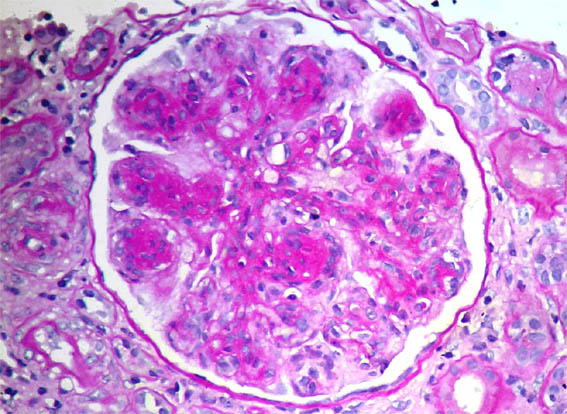

Figure 5.

PAS, X400.